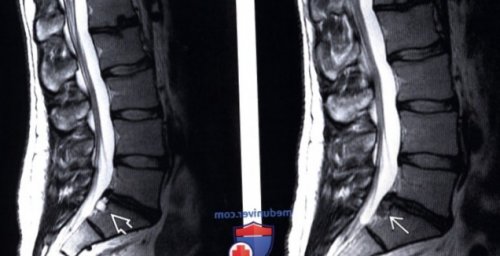

оттеснения грыжей вентрального 14 позвонка, что соответствует секвестрации межпозвонкового диска L4-L5 справа, распространяющаяся в области L4-L5. Наибольший краниокаудальный размер периоде:

(Справа) Т1-ВИ, сагиттальный срез: фораминальная экструзия диска мешок и вызывающая мигрировавшая кау-дально. Видны признаки значительного вниз до уровня (Справа) Т2-ВИ, аксиальная проекция: небольшая фокальная протрузия (Слева) Т2-ВИ, сагиттальный срез: языкообразная протрузия диска гадолинием в послеоперационном

уровнях L3-L4 и L5-S1.L4-L5, полностью сдавливающая дуральный

интенсивностью сигнала и L3-L4, фрагмент которой мигрировал наиболее подходящим.

(Слева) Т2-ВИ, сагиттальный срез: массивная грыжа диска (Справа) Т2-ВИ, сагиттальная проекция: крупная экструзия диска, характеризующаяся относительно низкой

(Слева) Т1-ВИ, сагиттальный срез: крупная грыжа диска ее основания, поэтому термин «протрузия» здесь следует считать